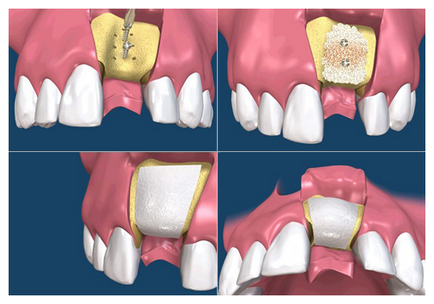

Пересадка аутогенного трансплантата

Здійснюється у вигляді пересадки блоку (фрагмента кістки пацієнта, іншими словами, аутотрансплантата) на ділянку, що вимагає збільшення обсягу кісткової тканини. У разі, коли резорбція (розсмоктування) кісткової тканини виражена занадто сильно, використовують методику «підсадки кісткових блоків». Забір аутогенного кісткового трансплантата виконується з внутрішньоротових донорських ділянок, таких як підборіддя або ретромолярній області (за 8-ками), бугорверхней щелепи і т.п.

Під місцевою анестезією з донорського ділянки забирається блок (шматочок кістки), який можна порівняти з розмірами відновлюваного ділянки. За допомогою спеціальних мініатюрних гвинтів блок прикручується до основної кісткової тканини в області дефекту, в якому попередньо робляться мініотверстія для проростання через них в блок нових судин і поліпшення кровопостачання блоку.

Простір між блоком і дефектом кістки заповнюється або аутогенного кісткової стружкою (отриманої при заборі блоку) або кістковим замінником. Блок з подсадочним матеріалом в залежності від технології операції може перекриватися чи ні ізолюючої мембраною. Далі обидві зони (і де забирався блок, і де він встановлювався) ретельно зашиваються. Через 4-5 місяців під місцевою анестезією проводять імплантаціію і видалення гвинтів.